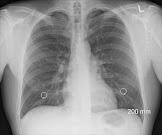

Što čovjek više puši, rizik po njegovo zdravstveno stanje je veći. Ako pušač puši 2 kutije cigareta dnevno, opasnost da umre od infarkta miokarda 2,5 puta je veća, a od raka pluća je 20 puta veća.